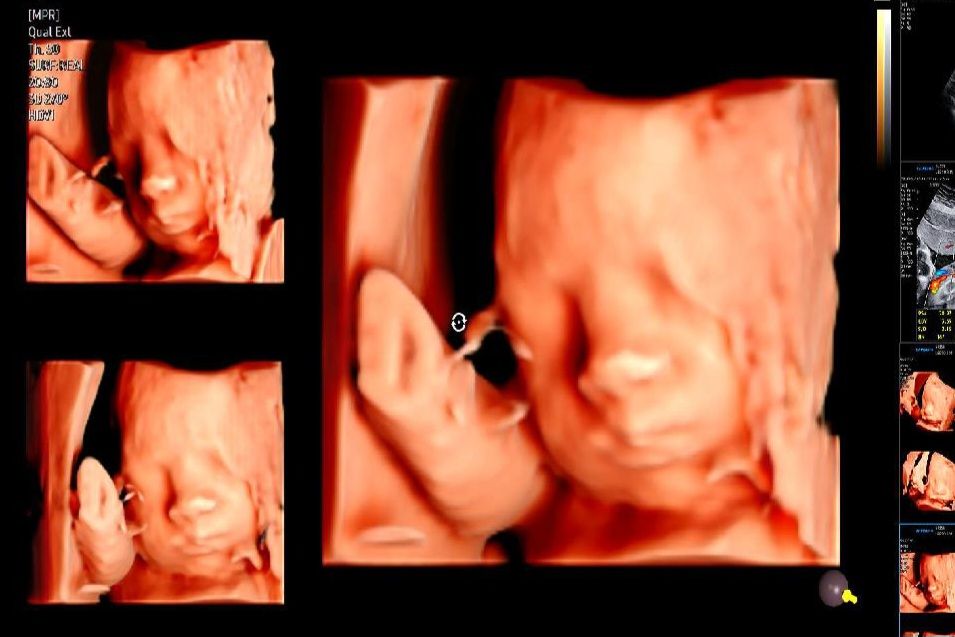

갈때마다 입초 찍어주시는데 오늘 29주5일 정밀검사 날이라 검사하고 왔는데 이제부터 3주마다 태동검사 시작이네요 첫째때 역아제왕이라 둘째도 자동제왕이라 원래 정상예정일은 4월12일인데 예상제왕은 3월말이라고 그때까지 잘 버티라고 이제 움직이지말고 자주 누워있으라고 하시더라구요. 페인버스터는 병원에서 무료로 지원해준다고는하는데 통증이 20-30퍼센트 정도만 효과있고 페인제로는 90-100퍼센트 효과인데 15만원이더라구요. 돈 내고 통증없이 페인제로가 낫긴 하겠죠? 제왕하시는분들은 어떤걸로 하시나요?